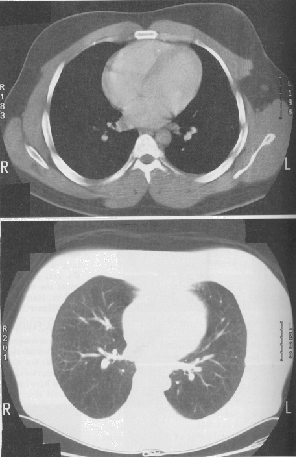

Por convenção, altos valores de CT são imageados como branco e baixos como preto. Como é impossível ao olho humano distinguir os milhares de coeficientes, utilizamos a técnica de janelas (windowing) para visualizar os valores dentro de determinada faixa. Um exemplo é a janela de mediastino na TC de tórax, na qual usa-se um CT de 500, variando entre -211 e + 289 com intervalos de 39. Os pulmões ficam bastante escuros nesta janela, uma vez que seu CT é muito menor. Para observar os pulmões é necessário mudar o CT em uma janela para que os pulmões sejam mais bem visualizados.

Fig. 1 - Diferentes nº CT avaliando uma mesma janela